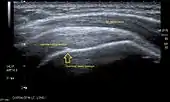

Longitudinal ultra sonography of the supraspinatus tendon

Ultrasound

There are several advantages of ultrasound. It is relatively cheap, does not emit any radiation, is accessible, is capable of visualizing tissue function in real time, and allows the performance of provocative maneuvers in order to replicate the patient’s pain.[26] Those benefits have helped ultrasound become a common initial choice for assessing tendons and soft tissues. Limitations include, for example, the high degree of operator dependence and the inability to define pathologies in bones. One also has to have an extensive anatomical knowledge of the examined region and keep an open mind to normal variations and artifacts created during the scan.[27]

After the introduction of high-frequency transducers in the mid-1980s, ultrasound has become a conventional tool for taking accurate and precise images of the shoulder to support diagnosis.[29][30][31][32][33]

Adequate for the examination are high-resolution, high-frequency transducers with a transmission frequency of 5, 7.5, and 10 MHz. To improve the focus on structures close to the skin an additional "water start-up length" is advisable. During the examination the patient is asked to be seated, the affected arm is then adducted and the elbow is bent to 90 degrees. Slow and cautious passive lateral and/or medial rotations have the effect of being able to visualize different sections of the shoulder. In order to also demonstrate those parts which are hidden under the acromion in the neutral position, a maximum medial rotation with hyperextension behind the back is required.[34]